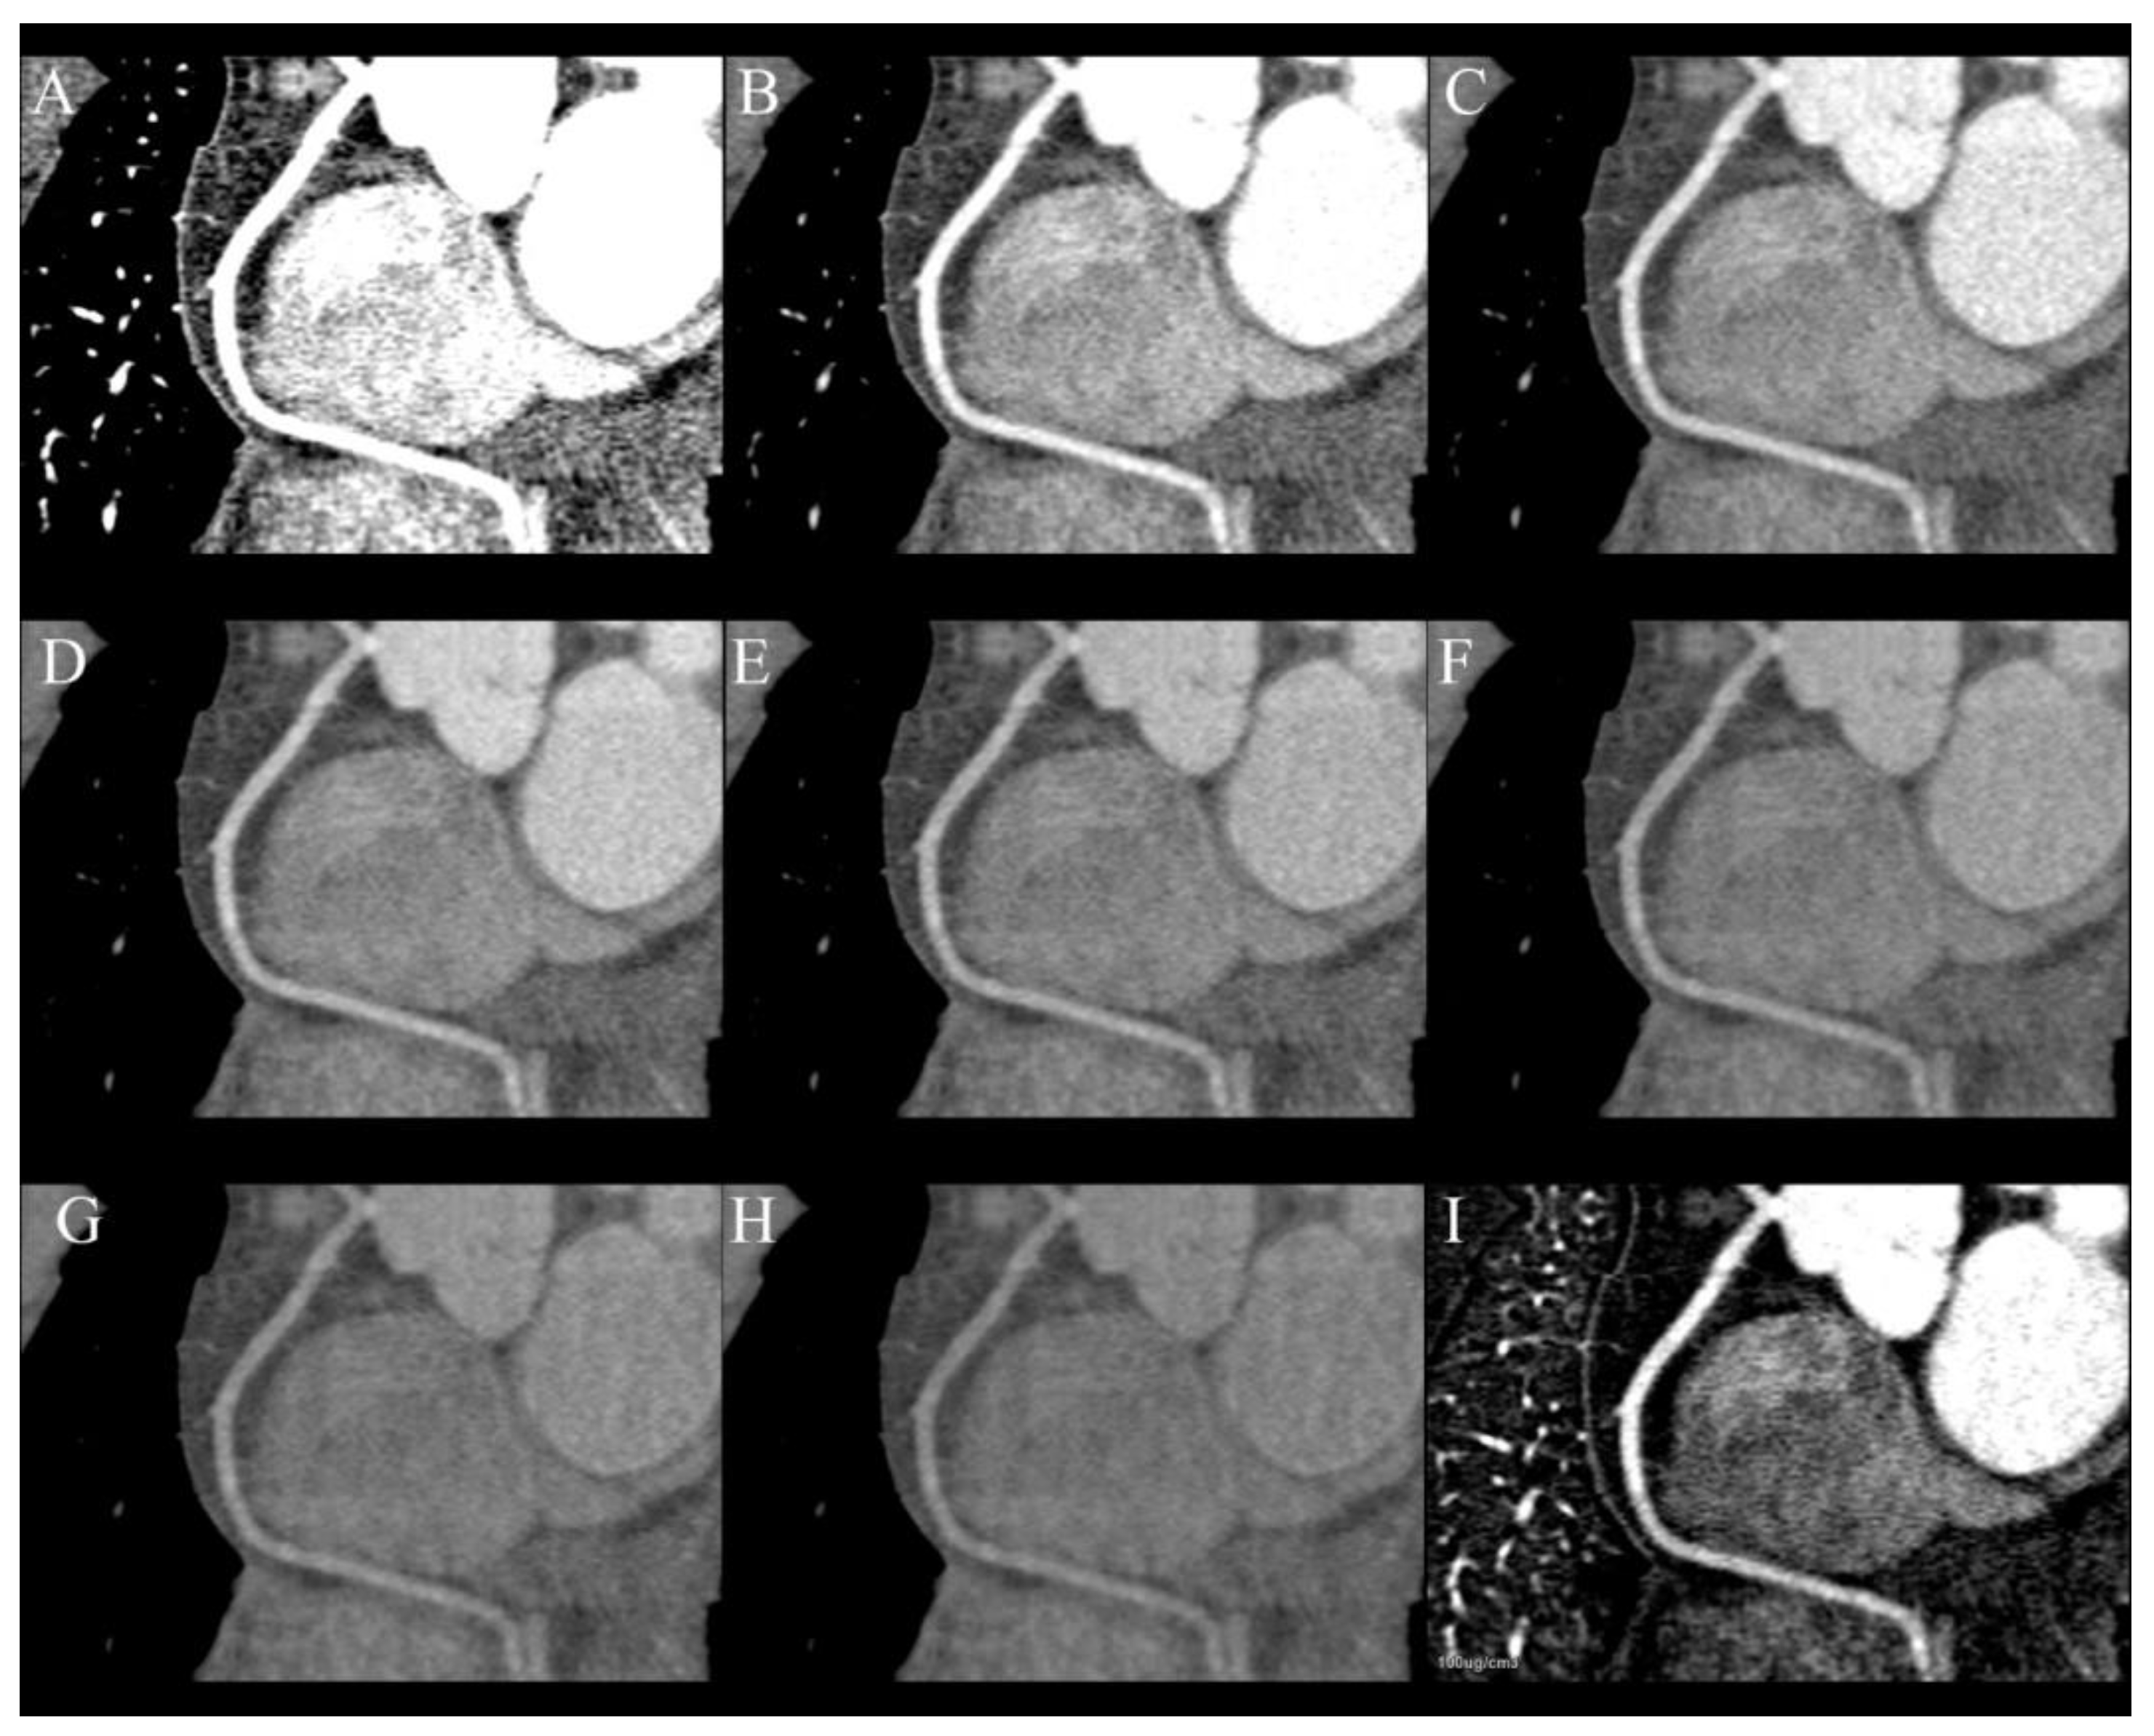

The primary goal of heart CT is the assessment of coronary arteries and improving quality and diagnostic possibilities is the main reason for performing this examination in dual-energy mode (Figure 2A–I). This is possible by reducing the number of blooming artifacts from stents and calcifications. Monoenergetic images, material specific reconstruction and effective Z-number imaging are helpful in reaching that goal [13,34]. The blooming artifacts that originate from stents and calcified plaques are a reason for the overestimation of the degree of stenosis. They can be reduced by VMIs of high energy, e.g., 110 keV, which has been proven to highly reduce artifacts from hyperdense metallic structures, but simultaneously, they are less sensitive to iodine. For that reason, it is essential to assess the lumen of coronary arteries using multiple VMIs. Calcium subtraction is other method of increasing the accuracy of heavily calcified coronary arteries [24,34,35].

Figure 2.

Series of curved MPR of RCA at different energy VMIs: (A)—40 keV, (B)—50 keV, (C)—60 keV, (D)—70 keV, (E)—80 keV, (F)—100 keV, (G)—120 keV, (H)—140 keV. The best contrast to noise ratio is at 60–70 keV images (C,D) Lower energies have higher iodine density but also much higher noise. Higher-energy VMIs (F–H) are less useful due to low contrast density. (I)—curved MPR reconstructed from iodine(water) map can also be used to assess lumen of RCA.

The same phenomenon makes the assessment of stents in lumen challenging. This problem was researched in detail by Hickethier et al. [36]. They reported that the amount and severity of blooming and beam-hardening artifacts depends on the stent’s material and its structure. The VMIs are significantly more effective in visualizing stents in lumen compared to standard polychromatic images as they reduce blooming artifacts, decrease noise and increase the contrast of images. VMI’s capabilities depend on the metal the stent is made of, e.g., stainless steel artifacts can be almost completely eliminated, while tantalum are just slightly reduced [36]. However, the research of Hickethier et al. did not take differences in stent structure into account, such as strut thickness, which is also related to a number of artifacts.

The degree of stenosis caused by soft plaques can be better assessed by using low-energy VMIs, e.g., 50 keV, which increase CNR and allows one to use a lower volume of contrast media [4].

Moreover, they can be used to salvage examinations with suboptimal vessel enhancement [9,13] (Figure 3) or to asses pulmonary and coronary arteries in a single examination without an extra dose of contrast—making each coronary CTA rule out examination.